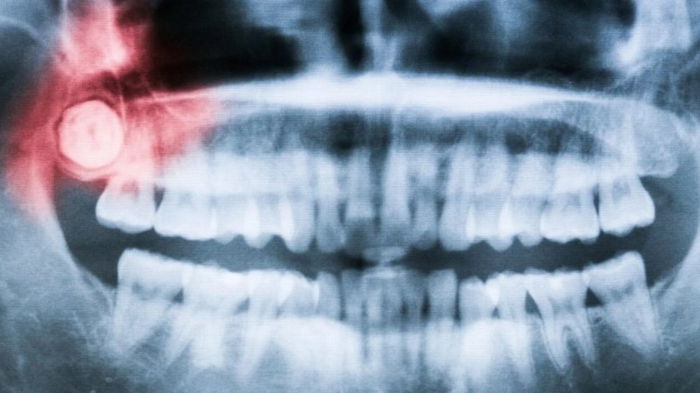

Большинство людей не помнят, как у них начали появляться первые зубы, но многие помнят, как прорезывались зубы мудрости и, конечно же о то, как их удаляли. В новом исследовании ученые предлагают свою версию того, почему зубы мудрости появляются так поздно, сообщает popsci.com По словам ученых, причиной позднего роста зубов мудрости может быть медленное развитие наших челюстей.

Наши зубы подвергаются значительному механическому давлению во время пережевывания пищи, как и вся структура челюсти. А это означает, что челюсть должна быть готова к развитию, чтобы зубы располагались по всей глубине рта, ближе всего к челюстному суставу. Если бы зубы мудрости появились раньше, они могли бы повредить челюсть, из которой выросли, говорит ученый. Все это результат двух важных особенностей у людей: у нас долгая жизнь и небольшое лицо. Жизнь у человека намного дольше по сравнению с другими существами на планете, например, с приматами. Мы развиваемся и у нас долгий период взросления. Также в отличие от приматов у нас довольно плоские и приплюснутые лица. Сочетание этих факторов означает, что наши челюсти не могут приспособиться к последнему набору коренных зубов до взрослого возраста. "Многим людям удаляют зубы мудрости, потому что некоторые считают их пережитком эволюции, который больше не нужен. Но их не обязательно удалять. Это нужно делать только в том случае, если они вызывают проблемы", — говорит Гэри Шварц. В любом случае, наши лица и медленное развитие, а также странное развитие зубов, — это часть того, что делает нас людьми, заключает ученый. | |